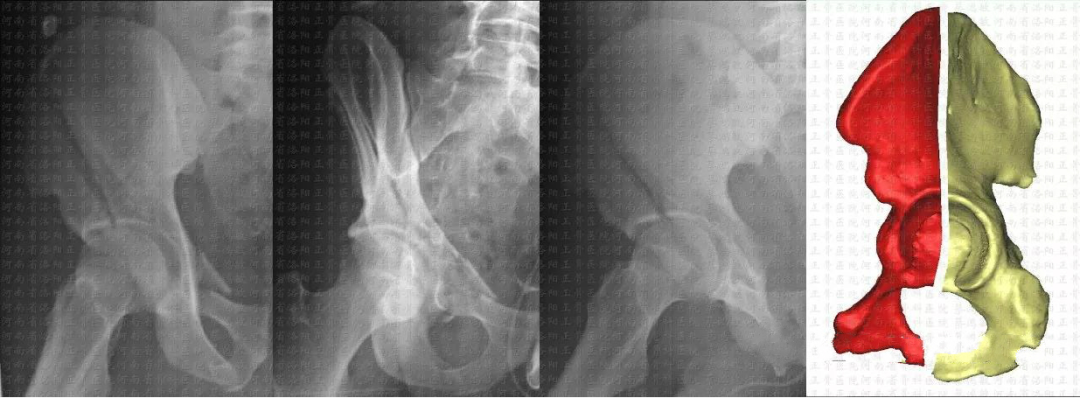

髋臼骨折分型

解剖(Judet-Letournel)分型:应用范围最广,临床指导价值最高。

简单(elementary)5型:后壁、后柱、前壁、前柱、横形复杂(associated)5型:后柱+后壁、横形+后壁、T型、前柱/壁+后半横形、双柱

复杂型    双柱骨折(23%)